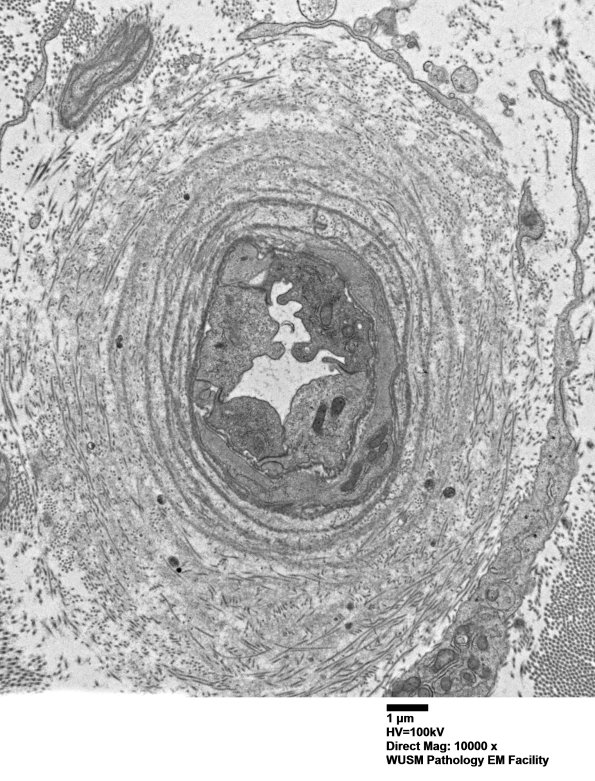

Washington University Experience | VASCULAR | Hypoxia-Ischemia, fetal-neonatal | White Matter | 13C2 (Case 13) EM024 - Copy

13C2 (Case 13) EM024 - Copy